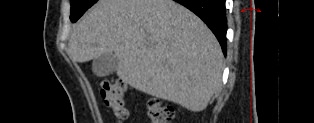

Мультиспиральная компьютерная томография желчного пузыря применяется для оценки состояния стенок желчного пузыря, изучения содержимого его полости, выявления воспалительных изменений, конкрементов и опухолевых новообразований.

Методика основана на применении рентгеновского излучения, с помощью которого томограф производит послойные срезы исследуемой области для получения изображений в мельчайших подробностях.

В клинике «Доступная медицина» исследование проводится на новейшем 128-срезовом томографе TOSHIBA AQUILION CXL, который позволяет проводить исследование за короткий промежуток времени при сниженной лучевой нагрузке. Посредством инновационных компьютерных программ томограф преобразует полученные данные в 3D-изображения желчного пузыря и желчевыводящих протоков. Это помогает диагностировать заболевания гепатобилиарной системы особенно при нетипичной клинической картине, когда при помощи других методов обследования (УЗИ, МРТ) не удается выявить причину нарушения оттока желчи из желчного пузыря.